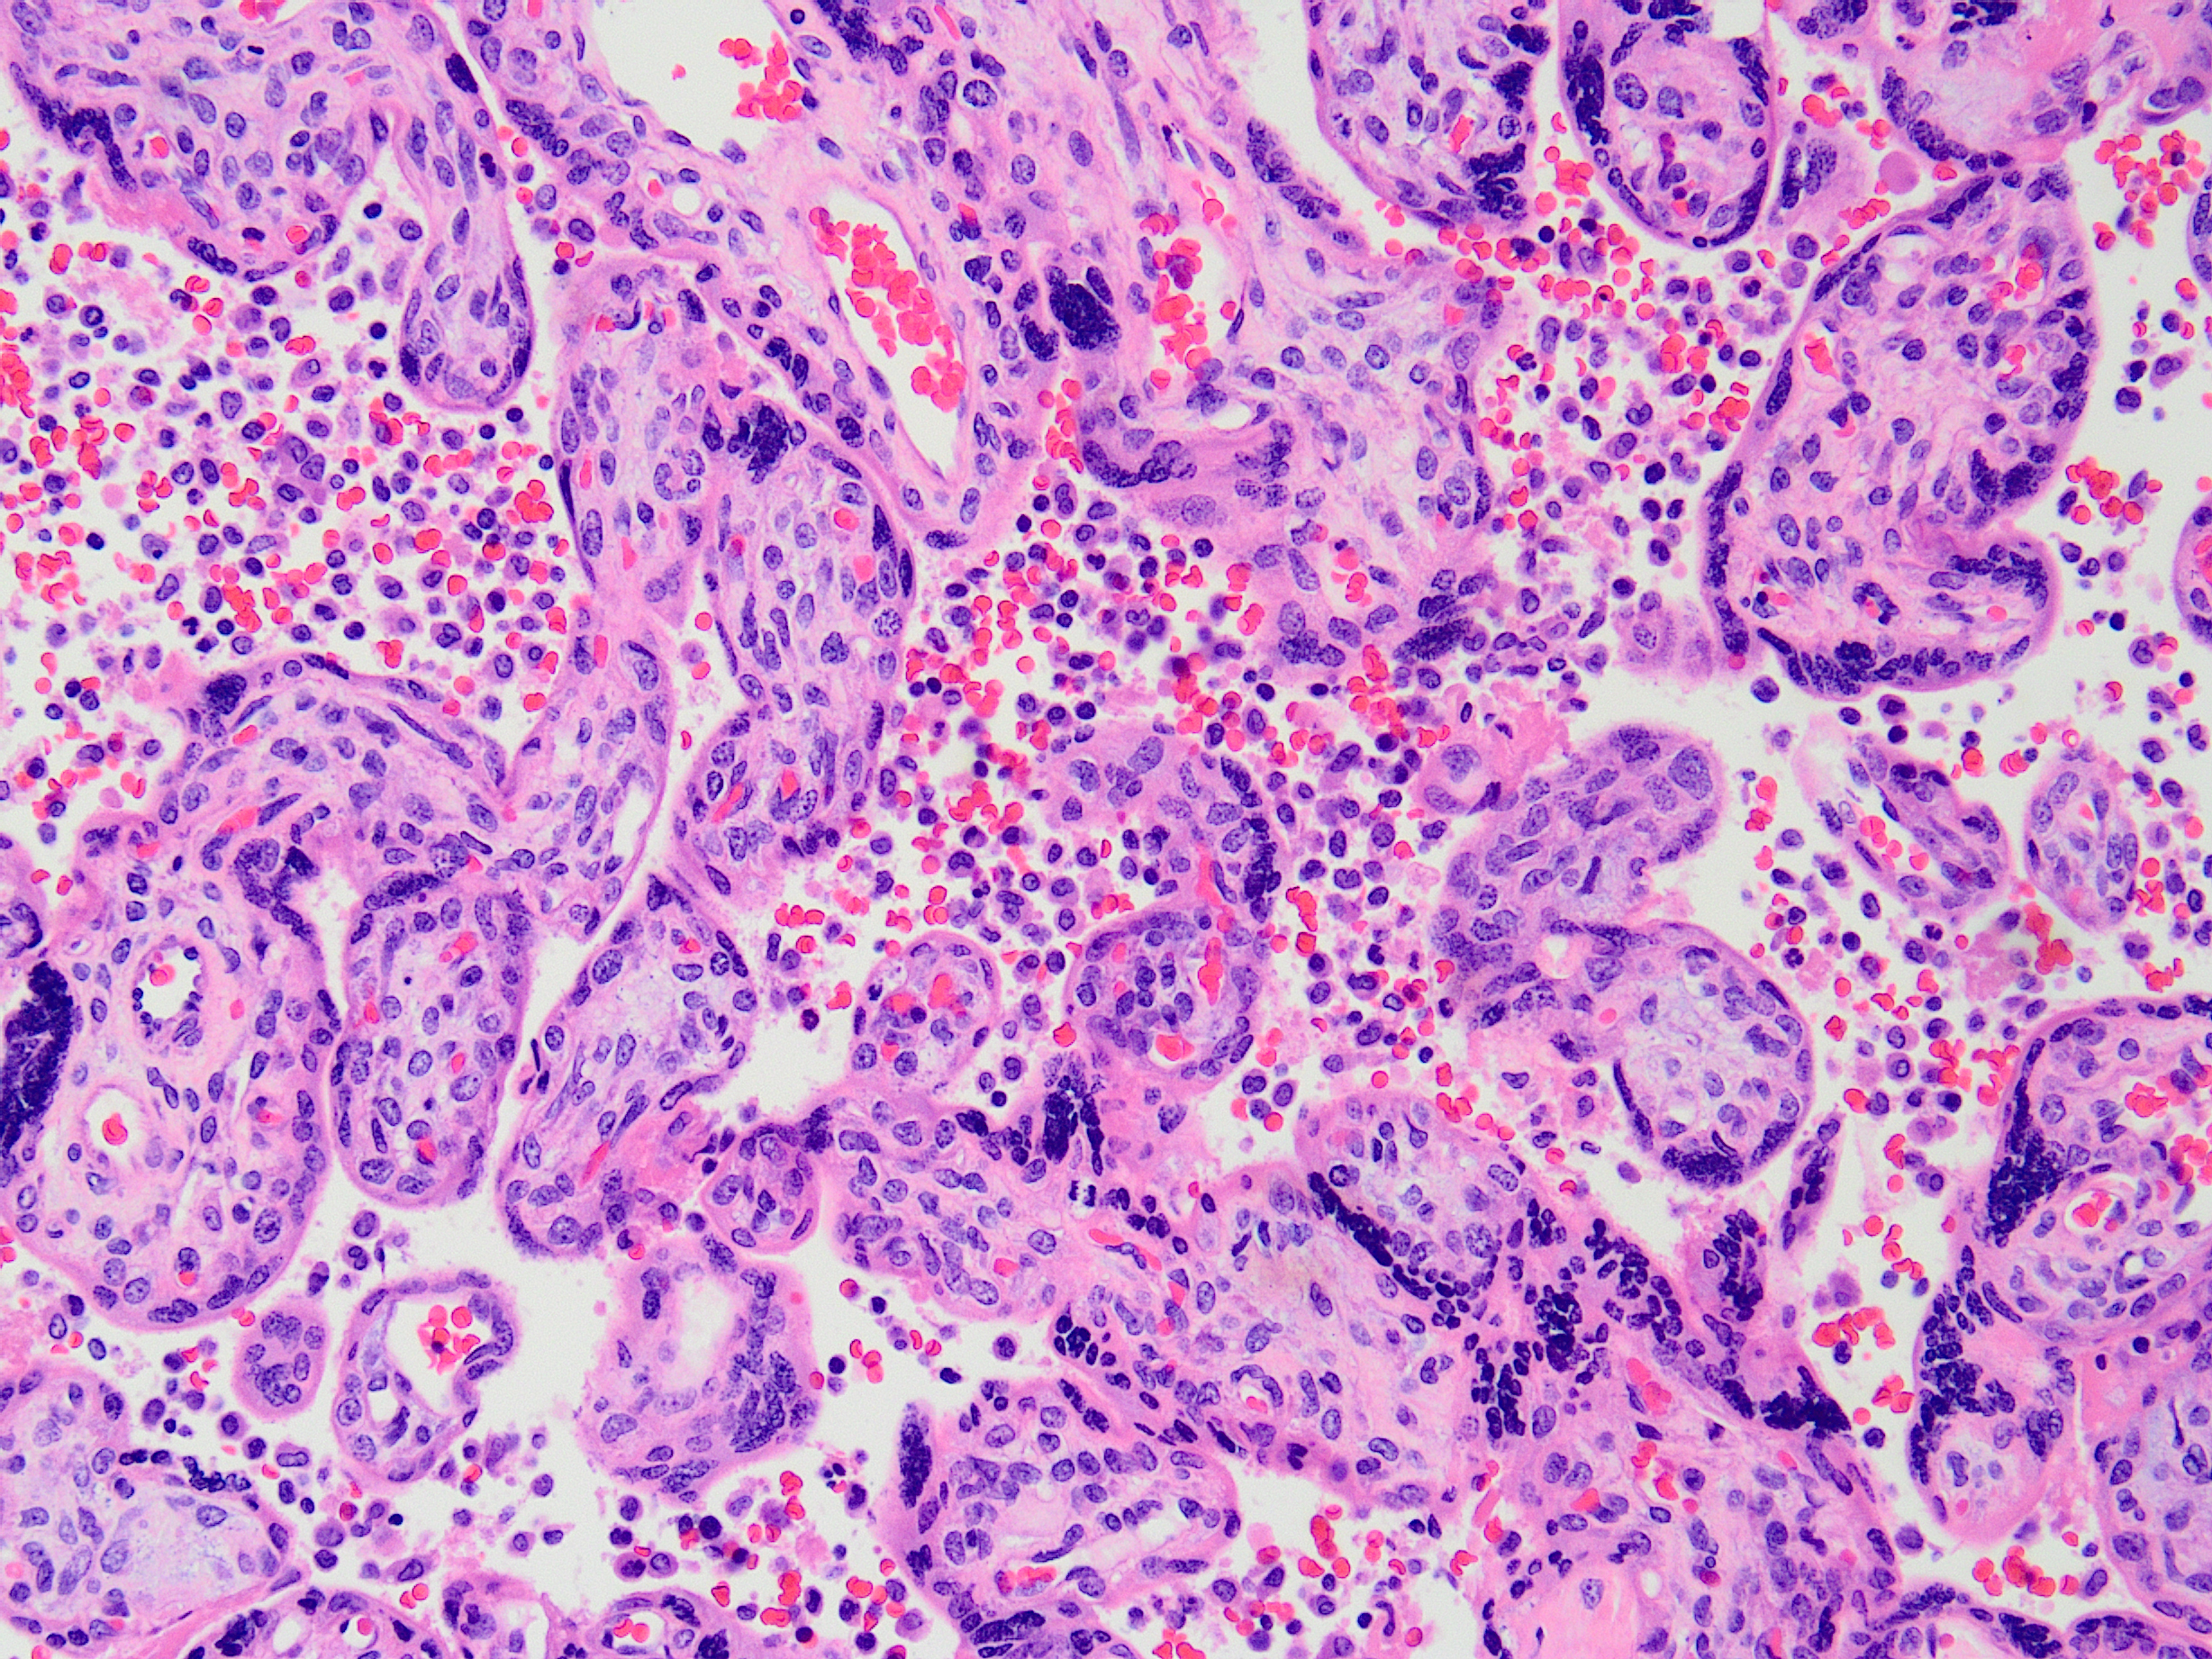

Case history

Placenta from a 33-year old P0 mother delivered at 25 6/7ths weeks. Maternal history...